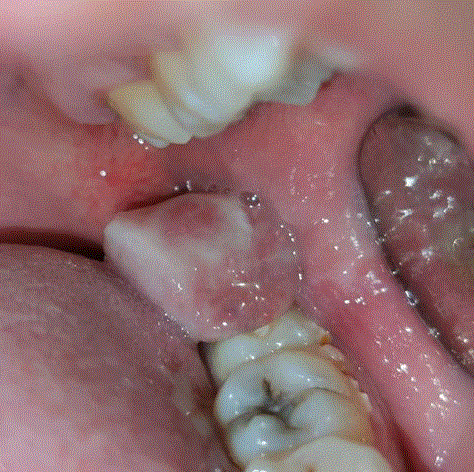

Beschreibe dieses Bild

Enoral zeigt sich ebenfalls die Auftreibung des Unterkiefers mit zentralem Ulkus und rötlichem, aufgeworfenem Randwall.